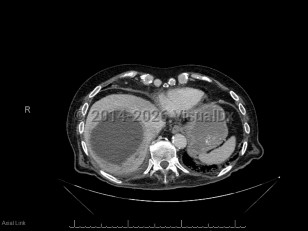

Pyogenic liver abscess

A pyogenic liver abscess is a collection of pus in the liver as the result of bacterial (or rarely fungal) infection.